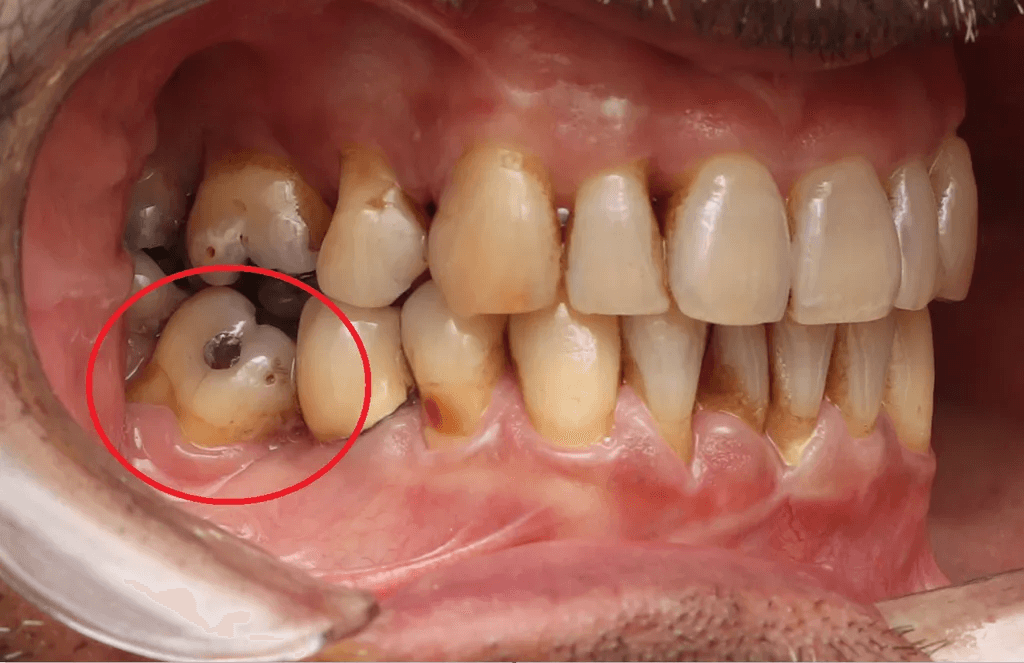

Doença Periodontal Ativa:

Pacientes com doenças gengivais avançadas podem não ser candidatos ideais para alinhadores, pois a movimentação dentária pode agravar a condição.

O tratamento ortodôntico em pacientes com doença periodontal deve ser realizado com muito critério e cuidado, sendo contraindicado o tratamento ortodôntico em pacientes com doença periodontal ativa.

Perda Óssea Significativa:

A perda óssea ao redor dos dentes pode comprometer a capacidade do alinhador de mover os dentes de forma eficaz e segura.

A movimentação ortodôntica pode exacerbar essa mobilidade, o que aumenta o risco de complicações como a perda do dente ou uma piora da condição da gengiva.

Achados radiolúcidos em radiografias podem ser indicativos de várias condições que afetam a saúde bucal e precisam ser considerados e avaliados antes de realizar movimentações ortodônticas. Alguns achados mais comuns são:

Cáries: Devem ser tratadas antes do início do tratamento ortodôntico, para evitar complicações, uma vez que a progressão da cárie pode afetar a estrutura dentária e saúde periodontal.

Lesões periapicais: Devem ser tratadas adequadamente com endodontia antes do início da ortodontia e acompanhamento radiográfico.